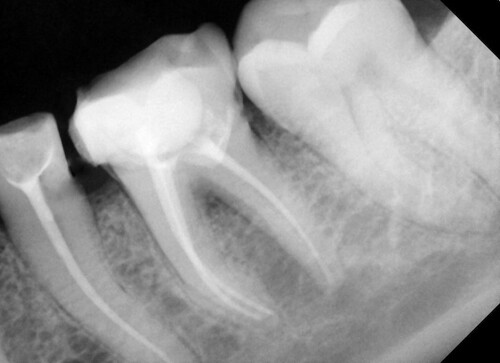

Клинический осмотр выявил наличие десневой ткани через отверстие доступа на нижнечелюстном левом первом моляре, что произошло в частной клинике (рис. 1). При рентгенографическом обследовании на левом первом моляре нижней челюсти была обнаружена перфорация на дистолингвальной стороне дна пульпы. На соседнем премоляре также присутствовал проксимальный кариес (Рисунок 2).

Рис. 2